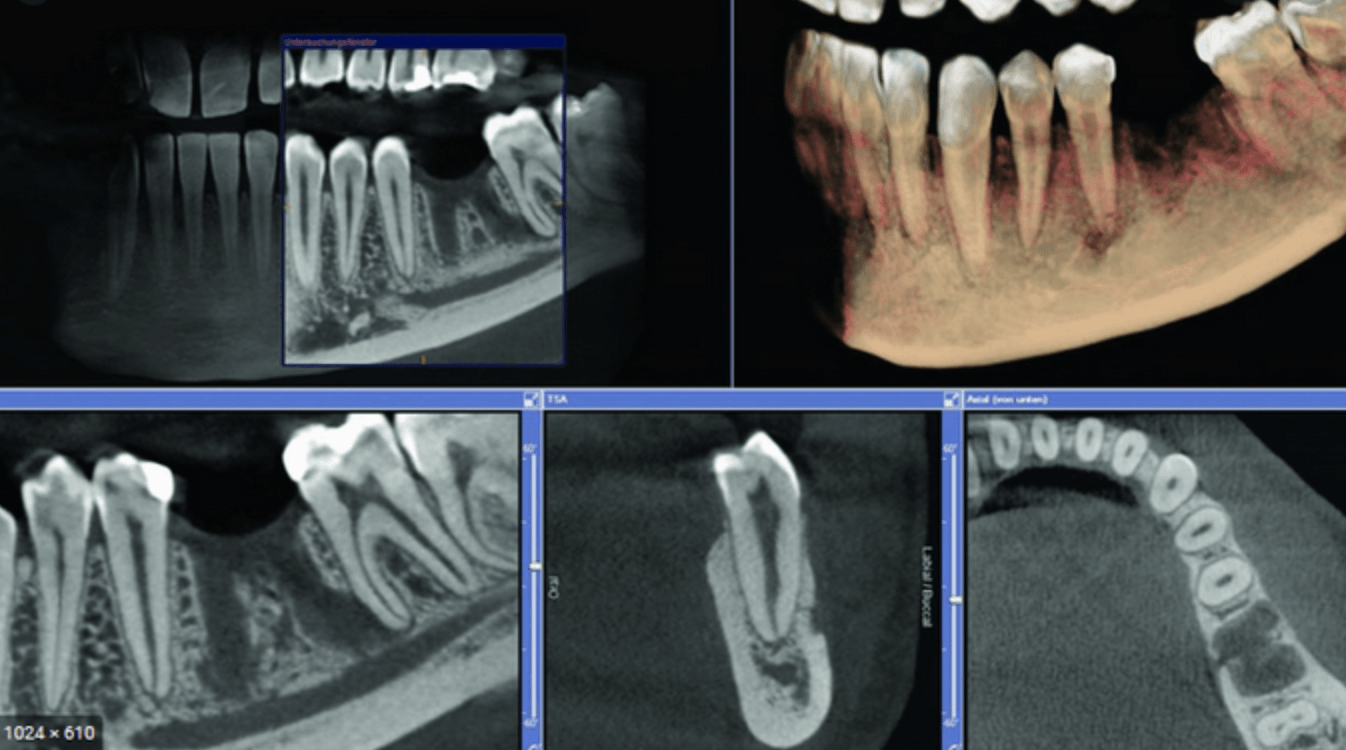

Konusinio pluošto kompiuterinė tomografija (CBCT arba kitaip vadinama 3D)

Konusinė (3D) tomografija

Gaunami trimačiai vaizdai, ypač tiksliai atkartojantys dantų ir žandikaulių anatomiją, parodo visus anatominius ypatumus bei uždegiminius procesus, leidžia tiksliau parinkti gydymo taktiką.